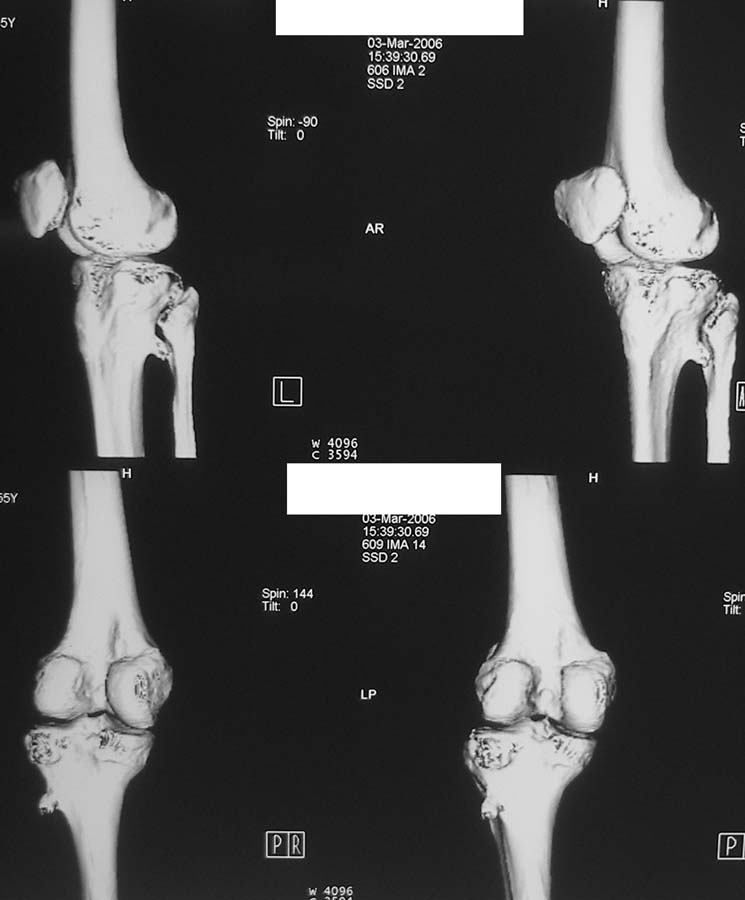

Женщина, 55 лет. С 2002 года - гонартроз. В настоящее время - боли в коленном суставе, стартовые боли, иногда в ночное время (проходит <от перемены положения ноги>).

Принимает НПВС, артрон-комплекс, внутрисуставно гиалган. Ревмопробы отрицательные. На рентгенограмме отметили сужение шейки малоберцовой кости, на спиральной КТ - экзостоз? Ваше мнение о целесообразности операции (велика вероятность повреждения нервов), предварительной биопсии?Спасибо! С уважением, А.В.Владзимирский Донецкий НИИ травматологии и ортопедии Донецк, Украина

Если боли связаны с гонартрозом, то показано тотальное эндопротезирование коленного сустава. Тип эндопротеза - мыщелковый, с сохранением задней крестовидной связки, сейчас таких моделей много (LCS, Balansis, Genesis, Scorpio, КЭКС-01 и другие, всё зависит с какими фирмами Вы работаете). Вопрос об удалении остеохондромы спорный, с одной стороны маловероятно ожидать у женщины 55 лет быстрого перерождения во вторичную хондросаркому при такой рентгенологической картине. Можно спротезировать коленный сустав и проводить рентгенконтроль каждые 6-12 мес. С другой стороны, если спротезировать и оставить остеохондрому, а она начнёт интенсивно рости, то её последующее радикальное удаление может ослабить тибиальный компонент эндопротеза. Проявляя онкологическую настороженность, остеохондрому лучше удалить первым этапом, до эндопротезирования с интервалом между операциями 6 мес. Производить биопсию в данном случае однозначно не целесообразно, так как при перерождении остеохондромы во вторичную хондросаркому на начальных стадиях малигнизации трудно гистологически отличить "добро" от "зла", и в этих ситуациях приоритет отдаётся рентгенологическим признакам. Техника операций при подобной остеохондроме стандартная - краевая резекция. Опасность повреждения малоберцового нерва существует всегда, но она зависит от мастерства хирурга и наличия микрохирургической техники (микроскоп не обязателен :)).

Вокруг коленного сустава беcсимптомные экзостозы встречаются очень часто, но они больше с медиальной стороны бедра и большеберцовой кости, и они выявляются при случайных рентгенологических исследованиях. Если нет сиптомов давления на малоберцовой нерв, то нет смысла из трогать, удаляется тогда, когда идет рост, поэтому только

наблюдение.

Насчет протезирования коленного сустава - при таком сохранном суставе навряд ли можно согласиться и совершенно согласен с Яковом, что надо искать источника боли сканированием или магнеторезонансными исследованиями.